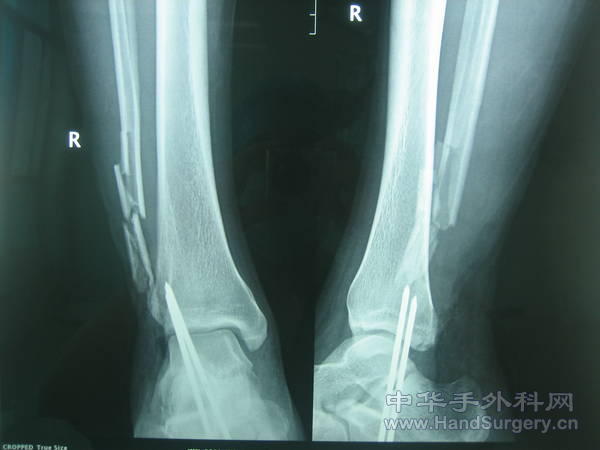

患者被皮带绞伤双足入院。右外踝骨缺损以及左内踝骨外露。

用了股前外以及背阔肌皮瓣修复。

右外踝取对侧腓骨小头重建。请大家指正,多提宝贵意见。

腓骨不带血运,右脚接胫前,左脚接胫后